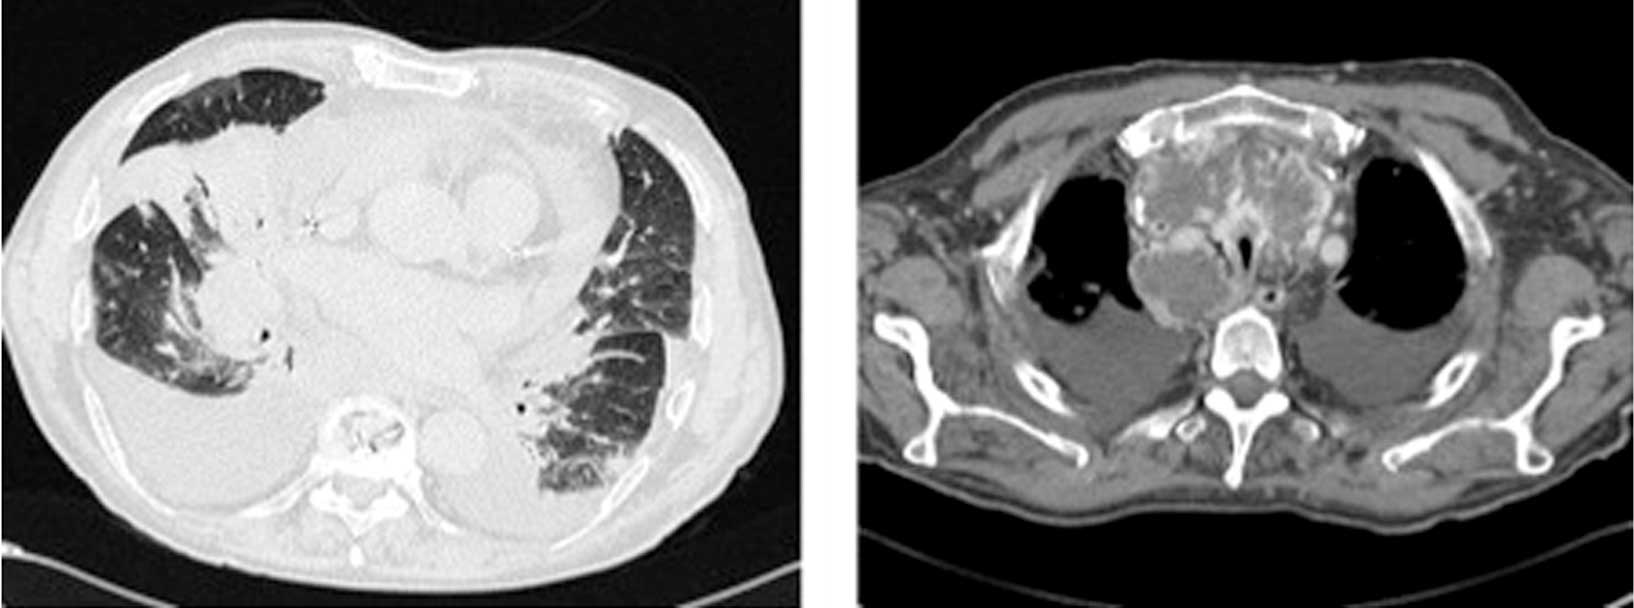

A 21-year-old male was admitted on the 17th of April, 2014 to the Department of Clinical Medicine and Rheumatology, Campus Bio-Medico University of Rome with fatigue, fever and a voluminous painless neck mass. The patient was referred on May 2, 2014 to hematologists. Venous blood tests showed the following: Hb, 12.6 g/dl; platelets, 428,000 cells/µl; WBC, 12,460 cells/µl (neutrophils, 10,370 cells/µl; lymphocytes, 690 cells/µl; macrophages, 1,240 cells /µl) and erythrocyte sedimentation rate, 120 mm/h. CT examination identified a voluminous solid mass with spiculated margins and internal necrosis, localized on the left anterior superior mediastinum. This mass caused severe compression of the left lung apex and jugular vein (Fig. 2). Subsequent echocardiography demonstrated pericardial effusion. A biopsy of the mass was performed with a menghini needle (Hepafix, B. Braun, Melsungen, Germany). The specimen was formalin-fixed and paraffin-embedded; 3 mm thick sections were cut and stained with H&E and observed with a BX51 light microscope (Olympus Corporation, Tokyo, Japan). Histochemical and immunophenotypic analyses were performed on additional sections. Histological examination revealed an unclassifiable B-cell lymphoma, with features that were indicative of diffuse large B-cell lymphoma and classical Hodgkin's lymphoma stage IIB (5). The patient was subsequently referred to hematologists on May 13th and began a bleomycin, etoposide, doxorubicin, cyclophosphamide, vincristine, procarbazine and prednisone chemotherapy regimen. The patient had four cycles of chemotherapy, and the control positron emission tomography comparison demonstrated a reduction of the mediastinal mass.

Figure 2.

Axial computed tomography without a contrast agent in the mediastinal window (right) and with a contrast agent in the parenchymal window (left) shows mixed lymphoma appearing as a voluminous solid mass with irregular margins, and internal necrosis in the left anterior superior mediastinum; compression of the left lung apex, jugular vein and the left common vein is observed.